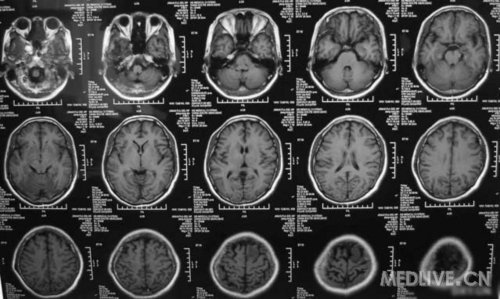

患者女,56岁,因右侧肢体活动不利2天于2011-06-15入院。查体:神志清,精神可,右侧肢体肌力4级,余无阳性体征。CT示左额叶占位,脑膜瘤可能性大。MRI示左额镰旁脑膜瘤,脑干左半亚急性梗塞。给予活血、神经营养、对症治疗,现一般情况好。请高手指点,何时手术切除脑膜瘤好啊?